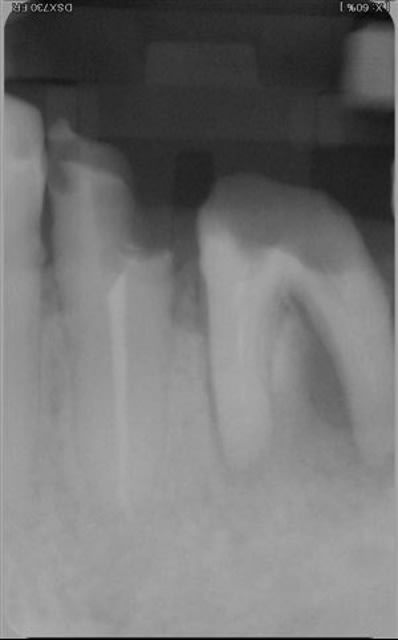

très belles endos ploc!

Pour la lésion endo paro sur la 46, j'aurai certainement extrait d'emblée.

Comme tu as fait un super boulot en endo, autant faire le max en paro maintenant. Il conviendrait de saquer la 48 mésioversée et lors de cette chir décoller un peu en antérieur, surfacer la racine distale et la zone inter radiculaire de la 46. Pas de matériau de comblement car il n'y a plus de paroi osseuse pour le soutenir.

Je reste tout de même pessimiste pour cette dent étant donné qu'il semble y avoir du tartre sur toute la hauteur de la racine distale. Quelle est la possibilité de réattache dans ce cas??? noah?

Je pense qu'il est bon de rappeler que tous nos actes endodontiques et parodontaux (pour ne citer qu'eux) sont basées sur des principes biologiques, qu'il est impossible de contourner.

La cicatrisation parodontale a largement été décrite et repose sur plusieurs impératifs cellulaires : présence de paroies osseuses, présence d'un ligt parodontal intact. Est ce des éléments présents dans le cas présenté .... non.

Tu peux toujours combler avec de la poudre de perlinpimpin, mais dépêches toi de faire une radio juste à la fin de ta chir, c'est le seul moment où tu auras le sentiment d'avoir régénéré de l'os !!

Il est tout aussi important de parler de pronostic que de parler de diagnostic. Et il y a des fois où l'extraction est la seule issue...